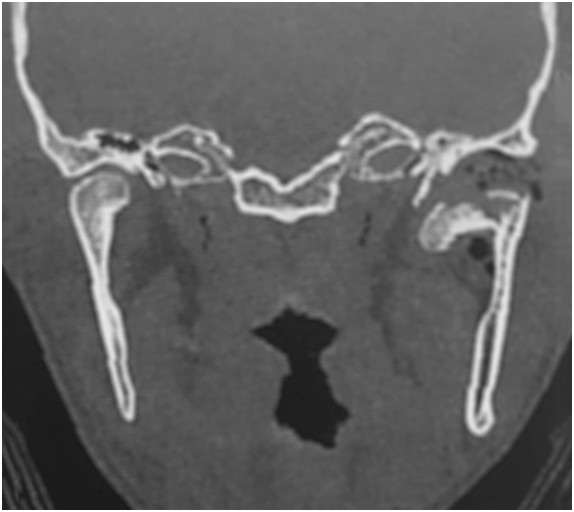

Rycina przestawia skan czołowy z tomografii komputerowej pacjenta po urazie. Wskaż prawdziwe stwierdzenie dotyczące złamania widocznego na rycinie:

Stwierdzono, że jednym z najstabilniejszych sposobów zespolenia odłamów w złamaniu podstawy wyrostka kłykciowego żuchwy lub niskiego złamania szyjki jest osteosynteza dwupłytkowa. Wskaż prawdziwe stwierdzenie dotyczące tej operacji:

Rycina przestawia kliniczno-anatomiczny podział budowy wyrostka kłykciowego żuchwy. Jakie wskazówki kliniczne z niego wynikają dla leczenia złamań podstawy i szyjki?